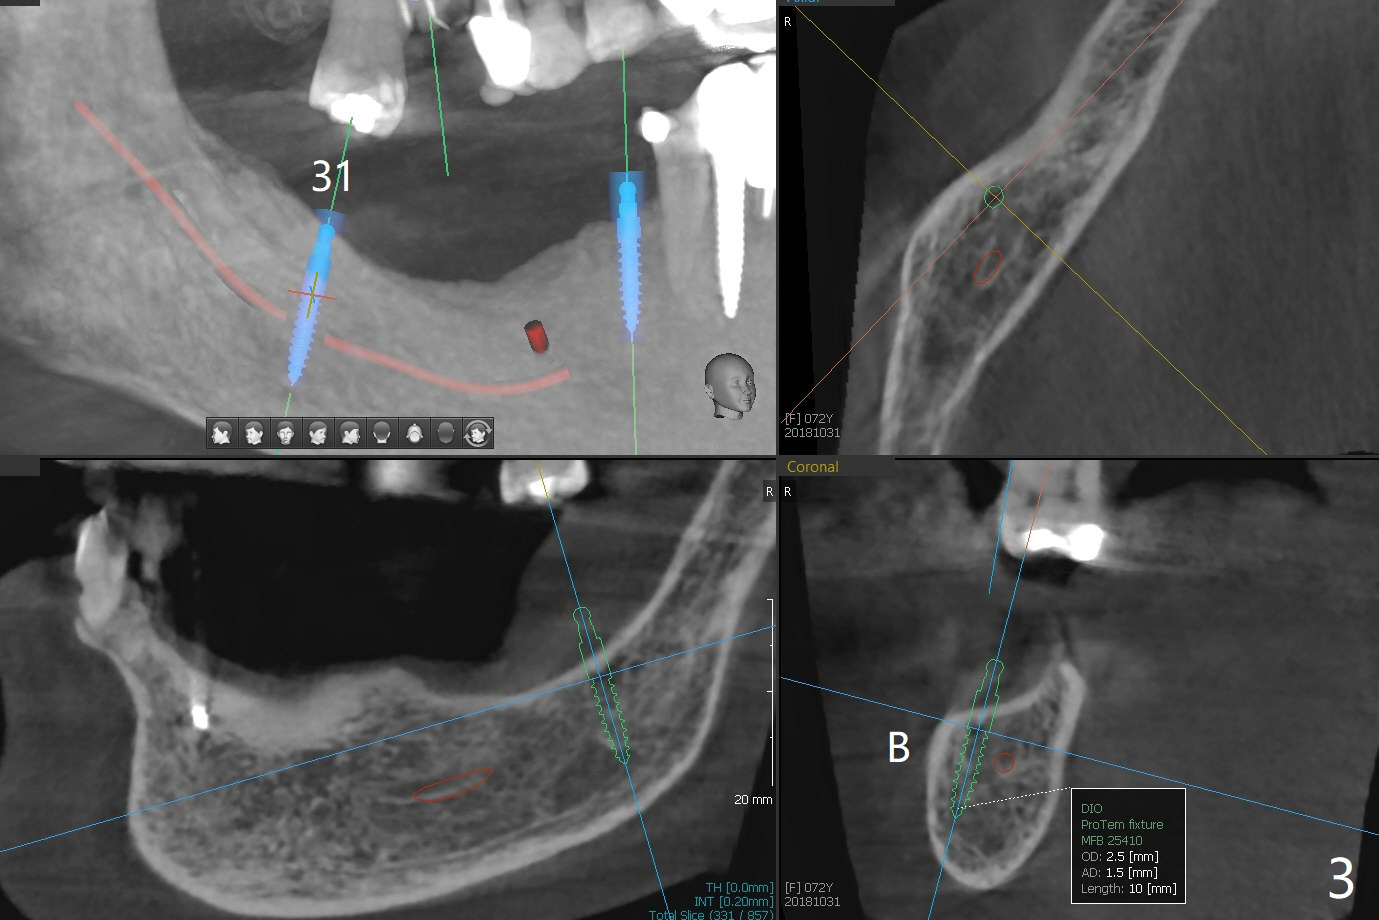

74岁女要求重做下颌局部托牙(图一(三年前(3号牙种植之前)拍摄)),因为lingual bar压迫牙龈,多次调整无效。准备在28和31牙位种植,做覆盖托牙(overdenture)。由于28牙位牙槽嵴窄,31牙位骨质短,准备使用导板植入2.5毫米一段式植体(图二,三),后者带有球状基台。